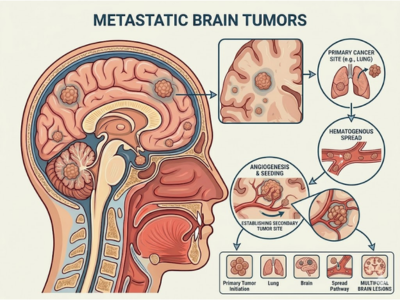

Metastatic Brain Tumors

These are brain tumors that spread from cancers elsewhere in the body.